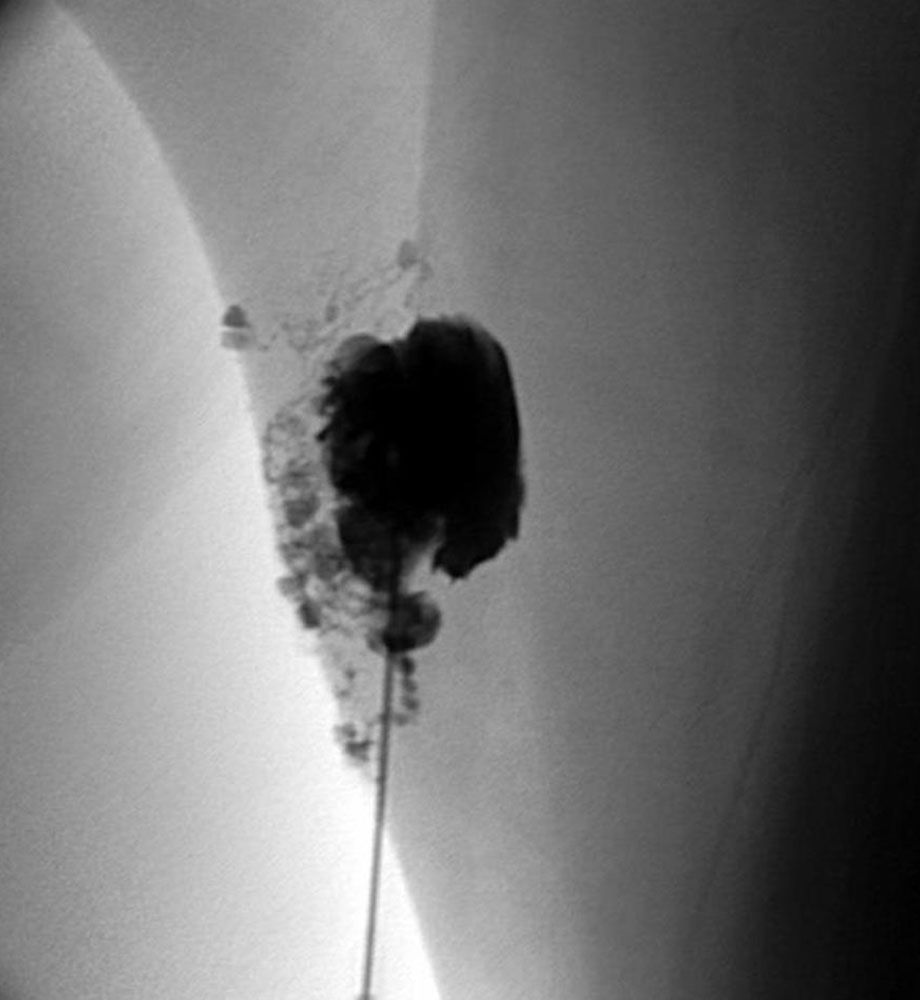

Vor allem makrozystische lymphatische Malformationen können durch eine Sklerosierungsbehandlung geheilt oder gebessert werden. Hier kommen die verschiedensten Sklerosierungsmedikamente zur Anwendung. OK 432 (Picibanil) ist ein japanisches Produkt bestehend aus Bruchstücken eines Streptococcus pyogenes, welches in eine Zyste appliziert zu einer entzündlichen Immunreaktion auf das Fremdprotein führt und die Zyste schrumpfen lässt. Das Antibiotikum Doxycyclin und das cytotoxische Medikament Bleomycin werden ebenfalls verwendet. Die Applikation erfolgt meist unter intraoperativer sonographischer Kontrolle. Häufig werden auch alkoholhaltige Substanzen wie zum Beispiel das STS (Sodium-Tetradecyl-Sulfat) oder Polidocanol unter sonographischer und radiologischer Kontrolle angewandt.

Manchmal wird dies kombiniert mit dem Einlegen eines Pigtail-Katheters, der bei starker postinterventioneller Sekretion das Gewebe entlasten kann und einen Zugang für eine wiederholte Sklerosierung ohne erneute Punktion darstellt. Dieses Verfahren ist sehr vorteilhaft, wenn man retropharyngeale Zysten behandeln will und den Atemweg sichern möchte. Bleomycin eignet sich besonders für kleinzystische Areale, die meist unter Sonographie infiltriert werden. Kutane oder mukosale Bläschen können gut mit Sklerosierung behandelt werden, neigen jedoch zu Rezidiven.